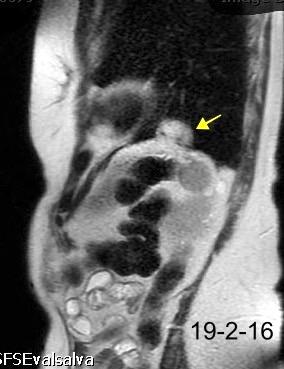

T1: Hipointenso

T2: Hiperintenso. Puede ser hipointenso. (Hierro)

Esplenectomía previa

Ferrer TM et al. Thoracic splenosis: History is the key. Respiratory Medicine Case Reports. 2017

Autotrasplante de tejido esplénico al tórax tras trauma. (T. Penetrante más frecuente que cerrado)

Causas:

1. Trauma 2.Esplenectomía

3. Diseminación hematógena

4. ¿Hipoxia?